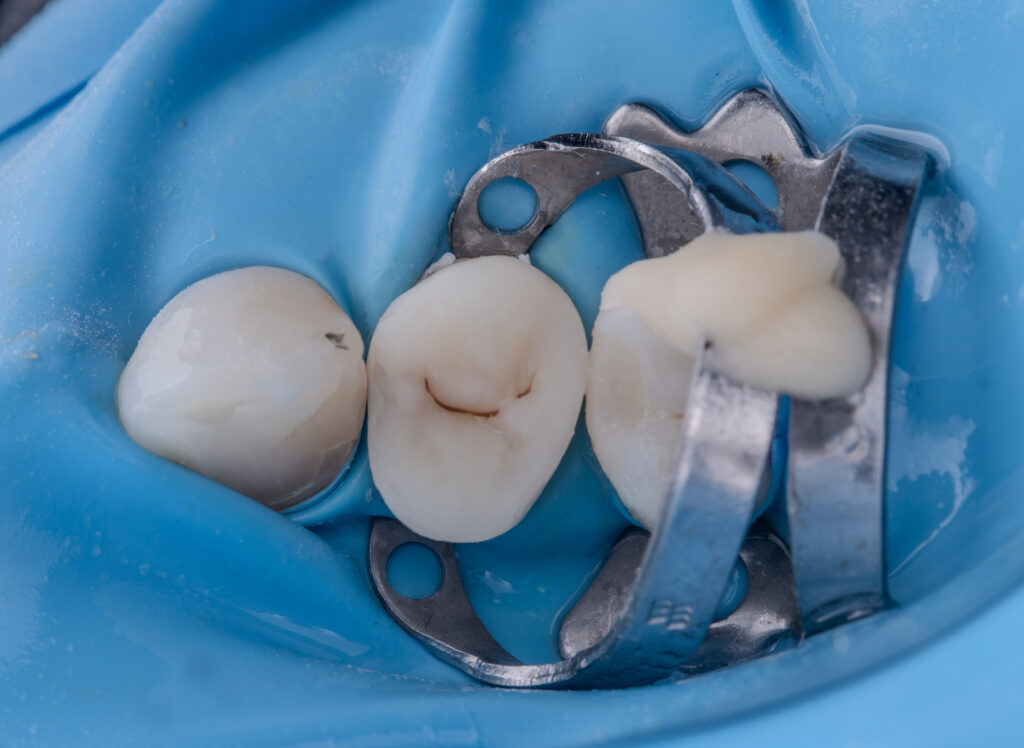

The second visit was dedicated to replacement of the old restoration and placement of a fiberglass post (EverX Dentin Shade was used), followed by restoration with Asteria A1B+, NeoSpectrum A2, and Enamel Brown stain.

The total time for restoration replacement was 1 hour and 30 minutes.